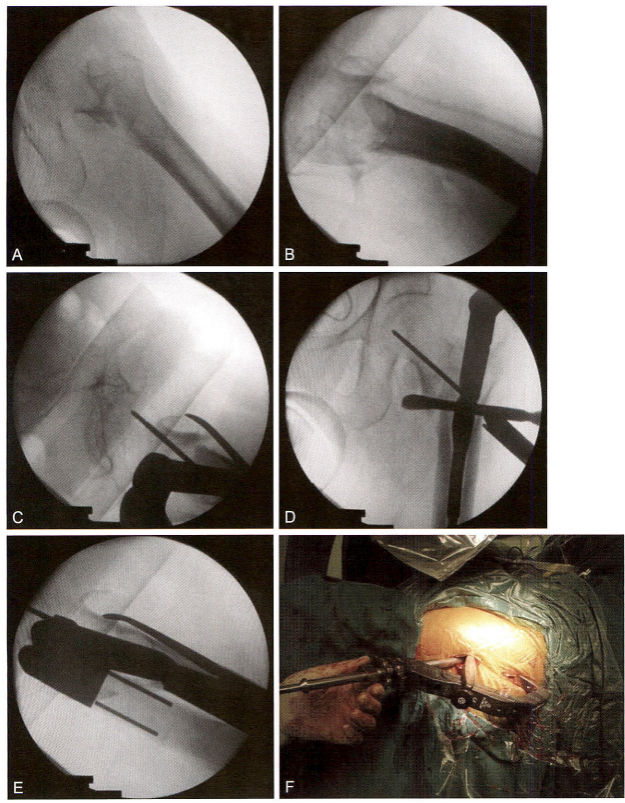

术中在肢体松弛的状态下,从螺旋刀片打入的切口插入器械进行复位。在手指的扪摸指引下,先用骨钩解除外上角的骨性交锁,再用剪刀 剪断紧张的骼股韧带和骼肌腱,解除软组织嵌顿造成的弹性交锁。在手 指的感知下牵引和旋转肢体,用骨钩牵拉头颈骨块下方的尖齿,头颈骨 块与股骨干即能获得满意的复位(对线、皮质对位)。再按常规操作,完 成闭合插钉内固定。

术毕透视,示骨折复位质量优(4分),内固定稳定性优(8分)。术 后三维CT 证实前内下角获得骨皮质对骨皮质的可靠支撑。术后1周,患 者在搀扶下可下地负重站立,练习行走。随访1.5年,骨折完全愈合(图 9-21)。

图9-21 小转子二分型难复位骨折。A.术前X 线片示股骨转子间二部分骨折,小转 子被骨折线平均分为上下两块,分别与头颈骨块和股骨干相连;B. 外上角骨性交锁 (箭头);C.三维CT重建图像,显示典型的移位特征:头颈骨块屈曲外旋,股骨干上 移短缩,头颈骨块下方骨皮质尖齿骑跨于股骨干前方

图9-21 ( 续 )D. 采用Mimics 软件模拟骨折复位,显示小转子从中部平分为上下两 块 ;E. 骨折移位特征示意图;F. 在打入股骨头导针和螺旋刀片的过程中,牵拉骨钩维 持复位;G 、H. 术毕正、侧位透视影像,示骨折复位良好,内固定位置满意;I 、J. 术 后1周随访X 线片;K 、L. 术后三维CT 显示前内下角骨皮质相互抵住、支撑(箭头), 稳定性优良,允许患者早期下地站立行走。★为小转子上半部骨块,从头颈骨块的下 方骨皮质尖齿上游离脱落,由于腰大肌的牵拉而向前向上移位。M、N. 术后随访1.5 年,骨折完全愈合